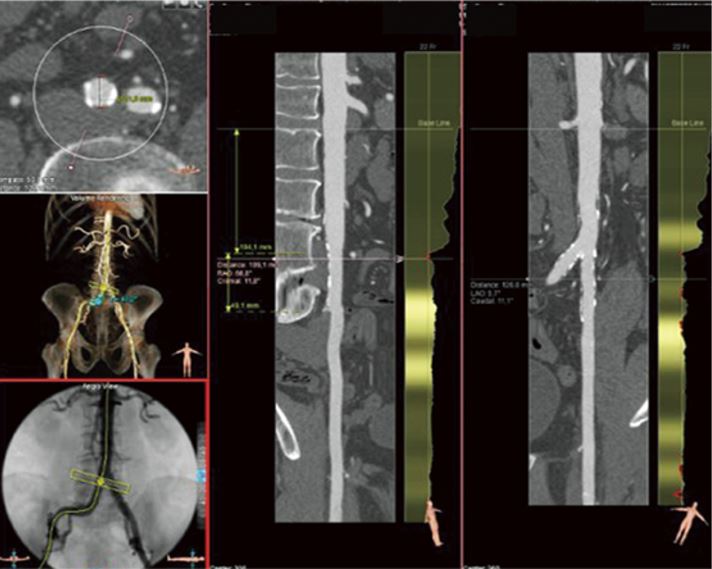

Програмне забезпечення Vitrea дозволяє візуалізувати та аналізувати 2D, 3D та 4D зображення анатомії та фізіологічних функцій за допомогою КТ (комп’ютерної томографії) та МР (магнітного резонансу), ПЕТ, ультразвуку та XR, що дозволяє медичним фахівцям заощадити час та має доступні інструменти для віддаленої роботи у мережі інтернет для ще більшої продуктивності. Програмне забезпечення включає: КТ аналіз печінки, КТ ендоваскулярне планування стента (EVSP), КТ нирки, КТ протікань (endoleak), КТ аорти, КТ сонної артерії та КТ Вілізієвого кола.

Важливі інструменти постобробки включають КТ-аналіз серця, КТ-аналіз мітрального клапана, КТ аорти, аналіз LAA, КТ планування TAVR та КТ планування електрофізіологічних процедур.